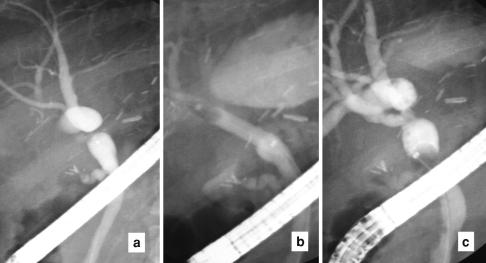

Biliary complications of living donor liver transplantation remain common. The complications of biliary leakage and stricture result in substantial recipient morbidity. A major focus of liver transplantation research is the prevention and reduction of these complications through identification of the multiple factors that are conducive to them. Such factors include the donor bile duct anatomy and quality, and the techniques of donor hepatectomy, recipient hepatectomy, and ductal reconstruction. A low threshold for re-exploration for possible bile leakage prevents development of uncontrolled sepsis. Return of good graft function can usually be expected after successful early endoscopic treatment. Contingent measures of percutaneous transhepatic dilatation and stenting, and revision hepaticojejunostomy have to be exercised with utmost care to avoid hepatic artery injury which may results in graft loss.